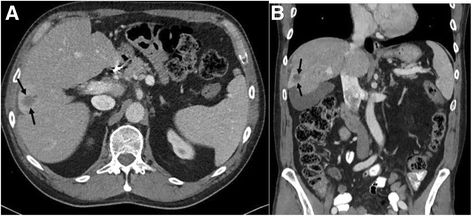

Case presentation: Here we describe the case of a 63-year-old man who presented initially with angiosarcoma of the nose and received surgery for the primary. Over 4 years he had recurrent disease in the face and liver and was treated with nab-paclitaxel, surgery, and radioembolization, but continued to have progressive disease. His tumor was found to express PD-L1 and he received off-label pembrolizumab 2 mg/kg every 21 days for 13 cycles with marked shrinkage of his liver disease and no new facial lesions. Secondary to this therapy he developed hepatitis and has been treated with decreasing doses of prednisone. During the 8 months off therapy he has developed no new or progressive lesions.